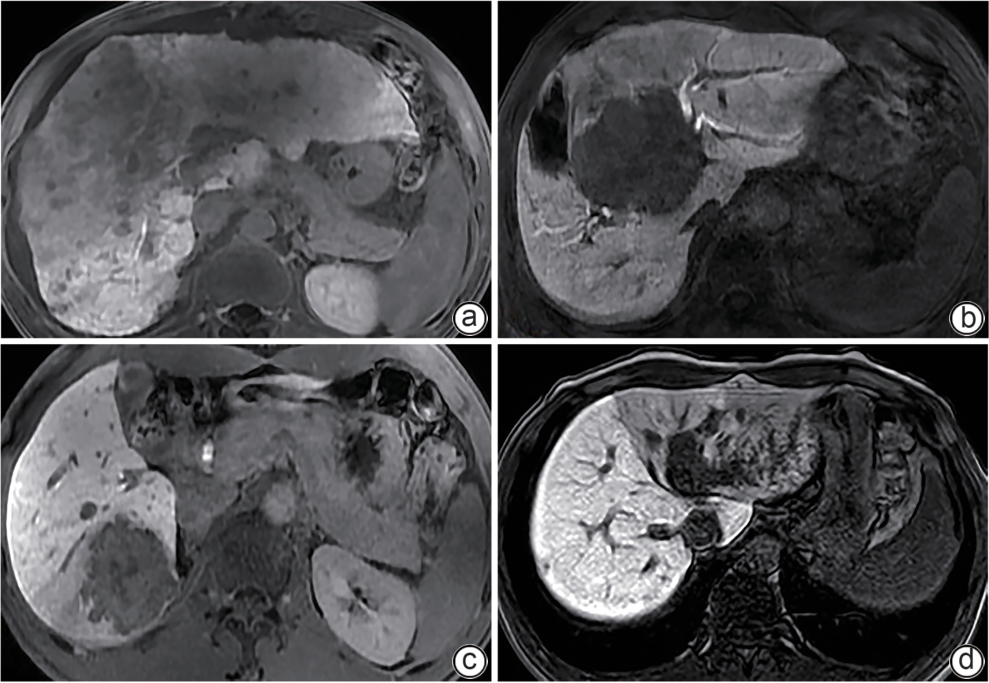

•   Objective  To establish a nomogram predictive model based on magnetic resonance cholangiopancreatography-related parameters and liver-to-muscle ratio, and to investigate the application value of this model in preoperative assessment of liver reserve function in patients with hepatic space-occupying lesion.  Methods  Clinical data and Gd-EOB-DTPA MRI imaging data were collected from 112 patients with hepatic space-occupying lesion who were hospitalized and scheduled for surgery in Wuming Hospital of Guangxi Medical University from April 2022 to April 2024. According to the degree of liver injury, the patients were divided into Child-Pugh class A group (65 patients with compensated liver function) and Child-Pugh class B+C group (47 patients with decompensated liver function, including 42 patients with Child-Pugh class B liver function and 5 patients with Child-Pugh class C liver function). The two groups of patients were measured in terms of liver-to-muscle ratio, relative signal intensity of the common bile duct, and bile duct score in different phases of contrast-enhanced CT scan, and univariate and multivariate Logistic regression analyses were used to identify independent predictive factors and establish a nomogram model. In addition, the receiver operating characteristic (ROC) curve, the calibration curve, and the decision curve were plotted to assess the discriminatory ability, accuracy, and clinical application value of the model. The independent-samples t test was used for comparison of normally distributed continuous data between two groups, and the Mann-Whitney U test was used for comparison of data with skewed distribution between two groups; the chi-square test was used for comparison of categorical data between two groups.  Results  There were significant differences between the two groups in liver-to-muscle ratio at 5 minutes (Z=-3.99, P<0.001), 10 minutes (Z=-4.39, P<0.001), 15 minutes (Z=-4.23, P<0.001), and 20 minutes (Z=-5.40, P<0.001) during the hepatobiliary phase, the relative enhancement degree of the common bile duct (Z=-4.85, P<0.001), and bile duct score (t=7.99, P<0.001). The multivariate Logistic regression analysis showed that liver-to-muscle ratio at 10 minutes during the hepatobiliary phase (odds ratio [OR]=0.63, 95% confidence interval [CI]: 0.44 — 0.90, P<0.05), liver-to-muscle ratio at 20 minutes during the hepatobiliary phase (OR=0.38, 95%CI: 0.17 — 0.82, P<0.05), and bile duct score (OR=0.17, 95%CI: 0.07 — 0.39, P<0.05) were independent influencing factors for the preoperative diagnosis of liver function decompensation. The nomogram model established based on liver-to-muscle ratio at 10 minutes during the hepatobiliary phase, liver-to-muscle ratio at 20 minutes during the hepatobiliary phase, and bile duct score had an area under the ROC curve of 0.905 (95%CI: 0.849 — 0.960), with a sensitivity of 78.7% with a specificity of 89.2%.  Conclusion  The nomogram model established based on the liver-to-muscle ratio at 10 and 20 minutes during the hepatobiliary phase and bile duct score can effectively assess the status of liver reserve function in patients with hepatic space-occupying lesion before surgery.